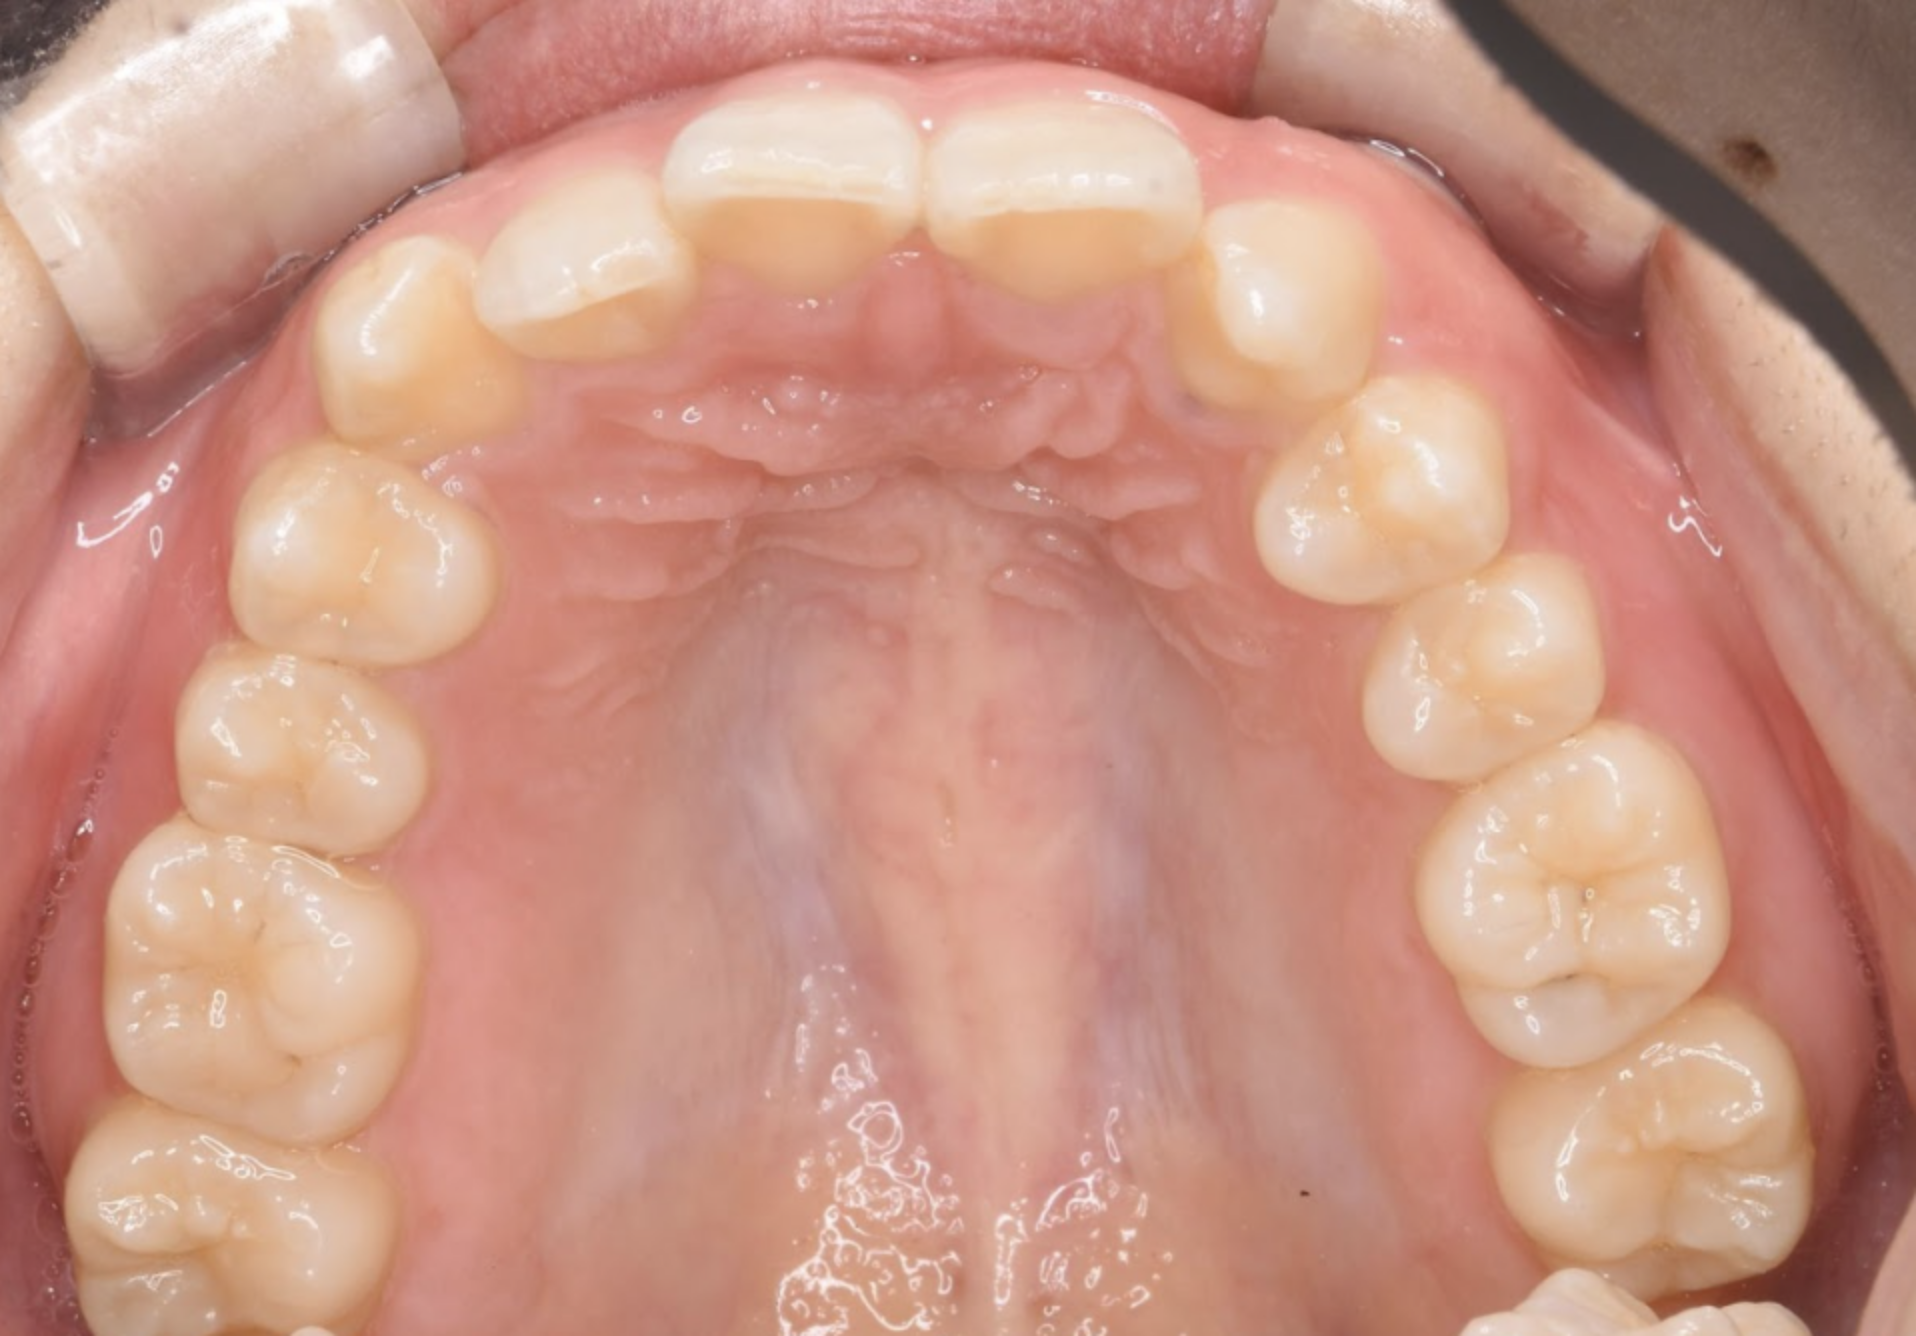

治療後の口腔写真

After